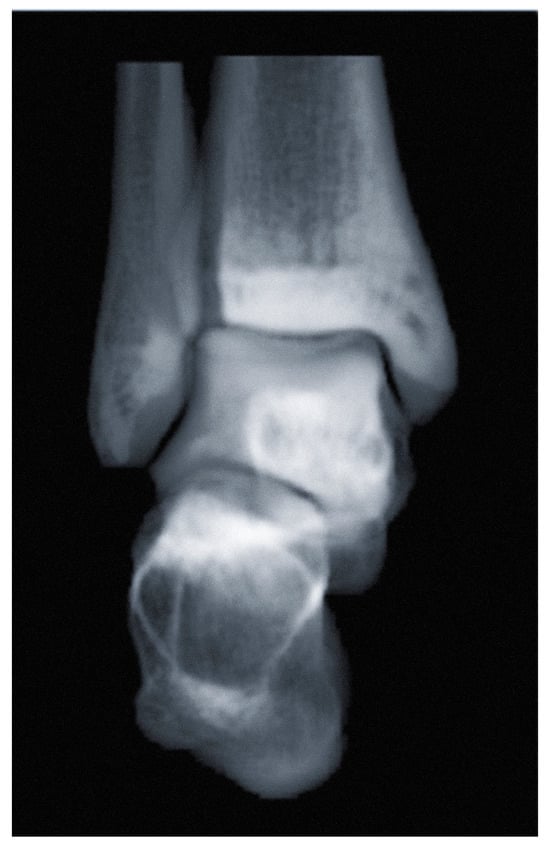

3.2. Syndesmosis Injury